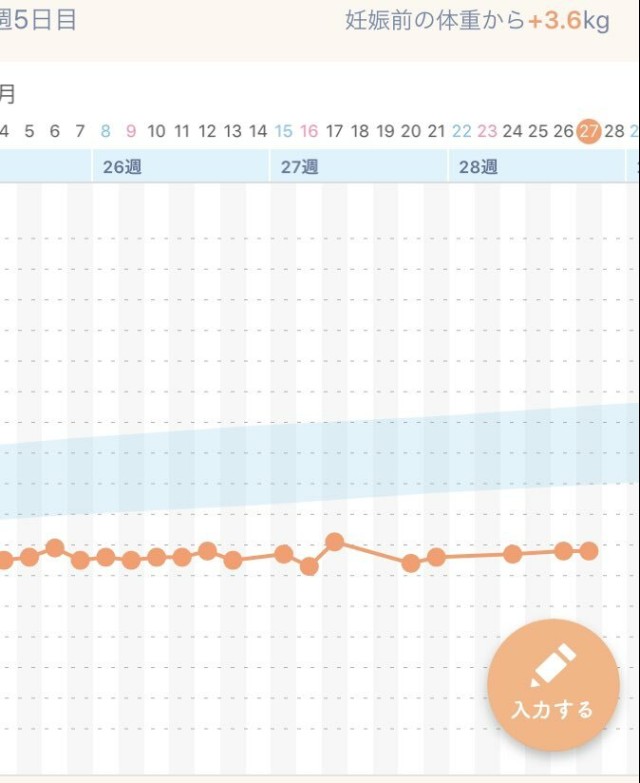

体重管理 妊娠前から体重増加+3.6kgで ずっと体重ほぼ変わらず?? 毎日1600kcalくらいしかとれてないからかなぁ(´・ω・`) 血糖値気にしながらカロリー摂るの難しすぎる。。